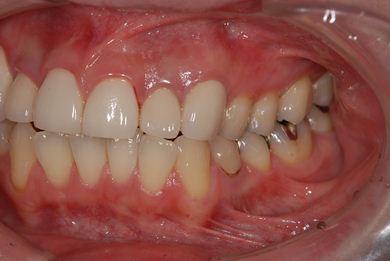

主訴 前歯2本の黄ばみが気になる。

治療前

• 治療前